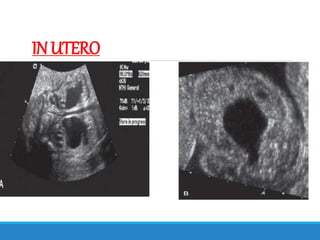

INUTERO(PRENATAL)

BY ANTENATAL U.S.G.

Oligohydramnios

Marked hydroureteronephrosis

Distended bladder

Thickened bladder wall

INUTERO

FETAL MRI

DILATED URETHRA

REDUCED AMNIOTIC FLUID LEVELS

LUNG HYPOPLASIA

CYSTIC CHANGES IN RENAL PARENCHYMA